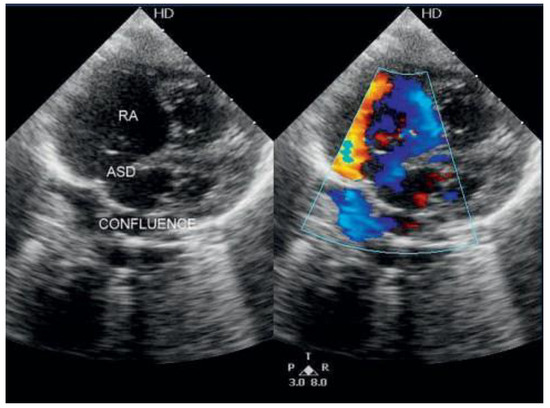

The fact that non-valvular (non-rheumatic) atrial fibrillation creates detectable thrombi in 17% of patients without oral anticoagulation and that 16% of the 17% (over 90% relatively) reside in the left atrial appendage (LAA), suggest that patients w...